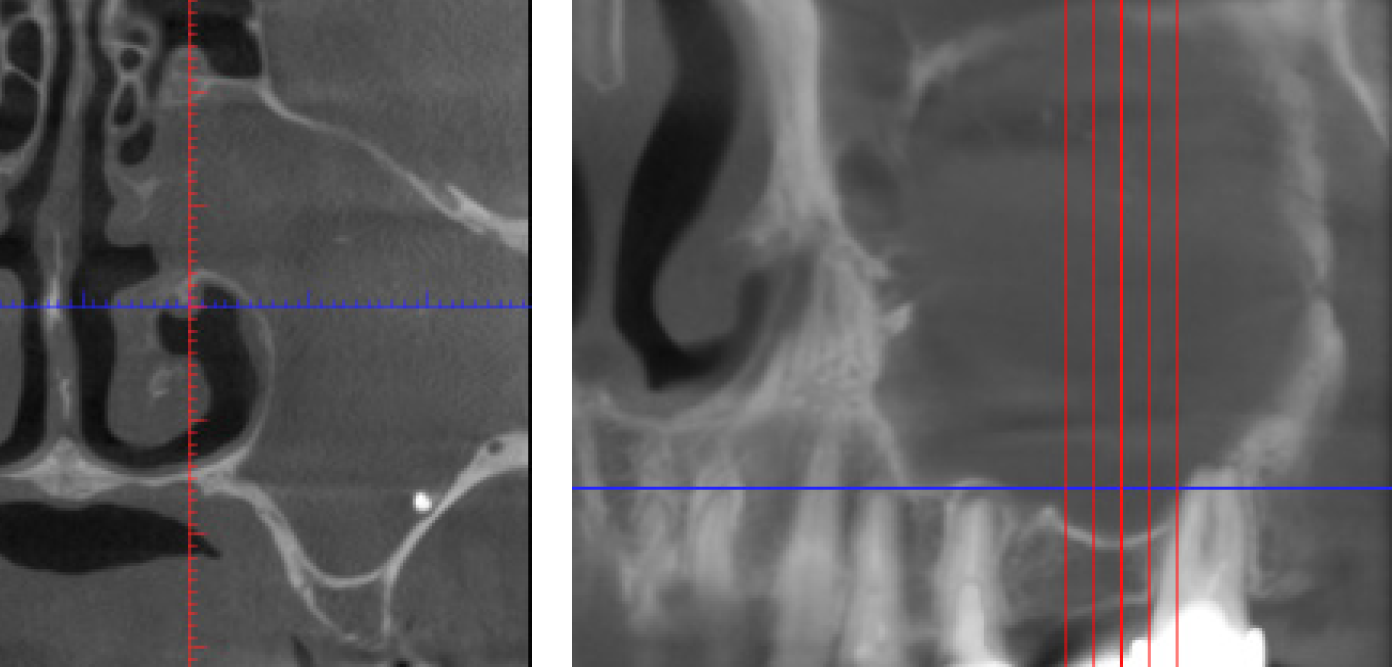

По данным КЛКТ получен следующий интерфейс: диффузное снижение пневматизации ВЧП слева, инородное тело (вероятнее всего, пломбировочный материал) в дистальной трети дна ВЧП слева, кистогранулемы в проекции верхушек корней зубов 2.5 и 2.7, целостность нижней стенки орбиты не нарушена, костно-дистрофической картины не визуализировано (рис. 2).

Рис. 2. Пациентка Э., предоперационное КЛКТ, вид ВЧП слева

Данные КЛКТ позволили детализировать нюансы зубочелюстной системы, в частности корней зубов, которые являлись причиной патологического процесса в полости ВЧП (рис. 4).

Рис. 4. Пациентка Э., предоперационное КЛКТ, вид ВЧП слева

Возможности реформатора КЛКТ позволили визуализировать максимальное количество сечений ВЧП и окружающих ее структур для дифференциальной диагностики и последующего успеха оперативного вмешательства (рис. 5).

Рис. 5. Пациентка Э., предоперационное КЛКТ, вид ВЧП слева